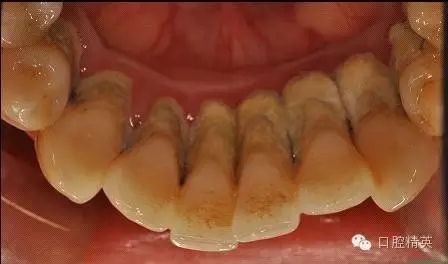

檢查見大量齦上及齦下結(jié)石,探診出血,牙周袋較深,32-42 II度松動。X線片顯示牙槽骨水平吸收。

治療前:

齦下刮治術(shù)(subgingival scaling),即根面平整術(shù)(root planing),是用比較精細(xì)的齦下刮治器刮除位于牙周袋內(nèi)根面上的牙石和菌斑。做齦下刮治時,醫(yī)生會使用一些專用去除袋內(nèi)結(jié)石的器械,刮除袋內(nèi)結(jié)石、細(xì)菌和受細(xì)菌感染組織。由于進(jìn)行該項操作需將器械伸入袋的深部組織內(nèi),既要刮盡齦下牙石(有時還要刮除牙根表面的壞死組織),又要盡量避免多損傷牙周組織。這就需要有較高的技巧,只有經(jīng)過專門訓(xùn)練的專業(yè)技術(shù)人員才能完成。